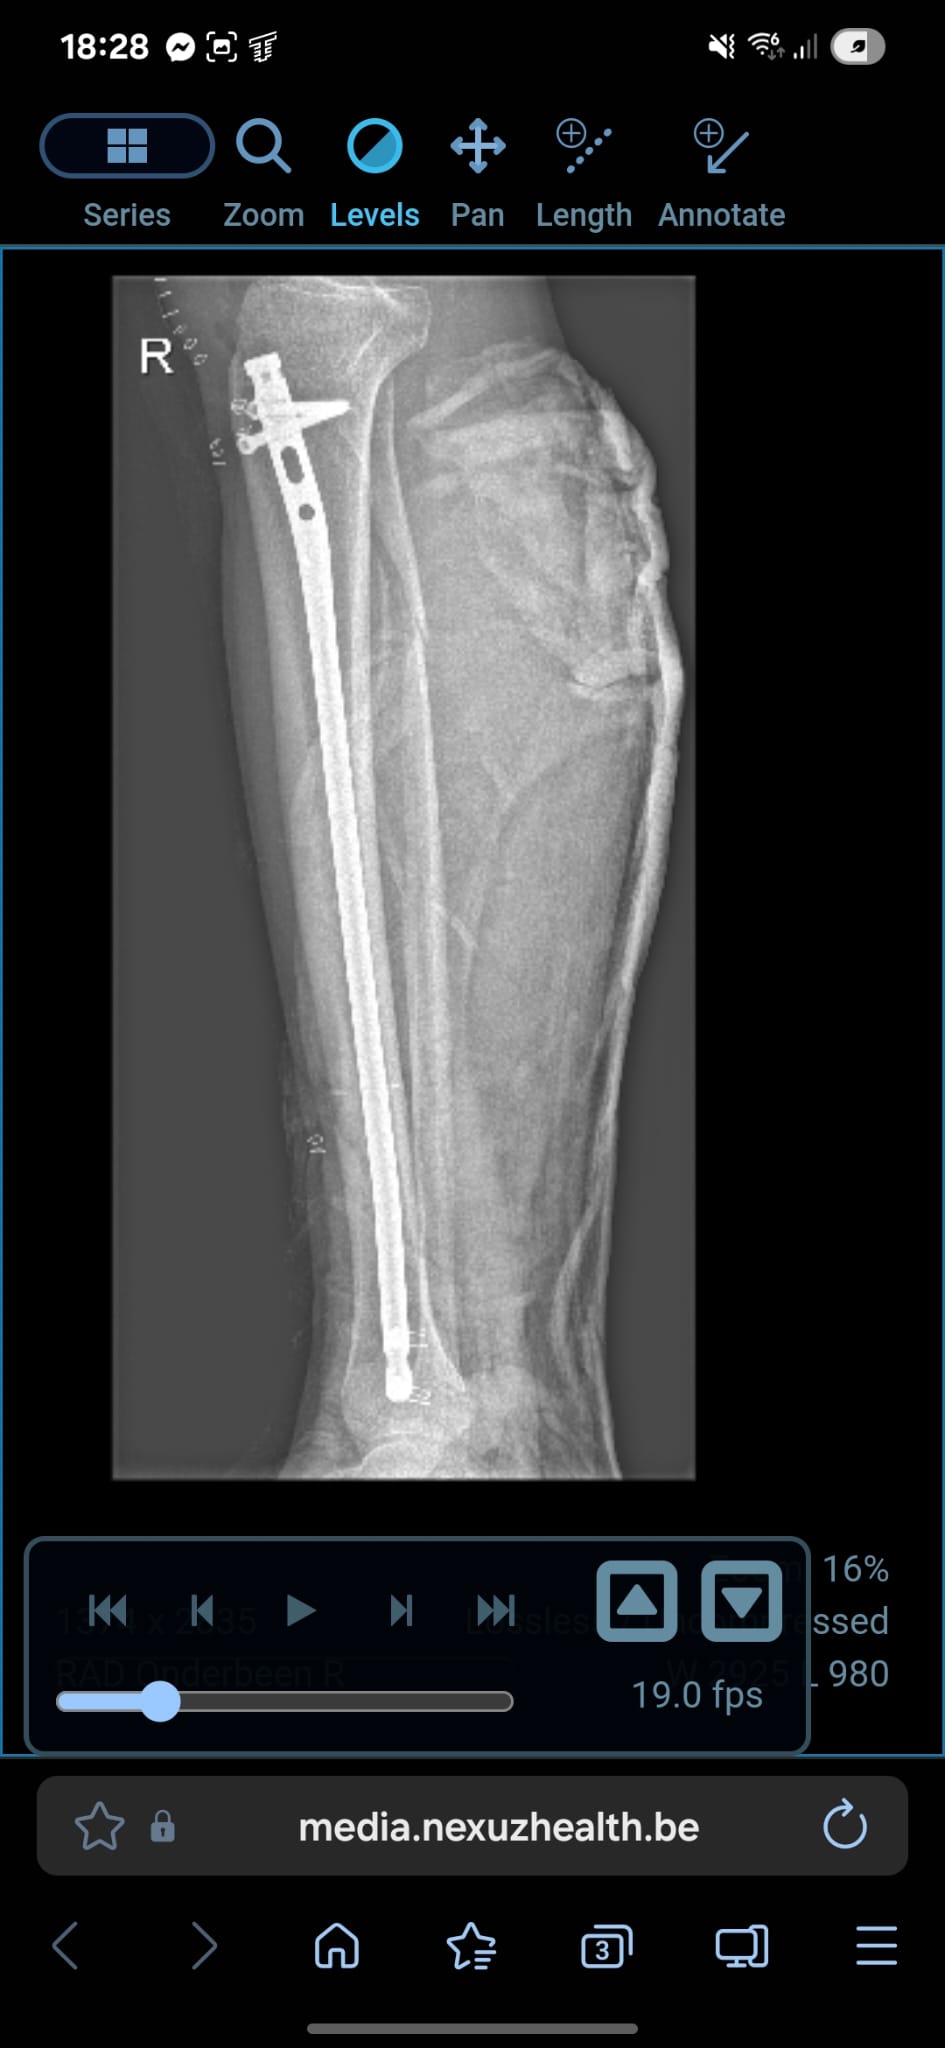

Bij deze mijn ervaring van 9 okt 2025

Ik zou je eerder een e-fiets van 25km/u aanraden, ideal compromis tussen veilgiheid, afstand en prijs.

Als ervaren motard die geregeld laagvliegt met race machientjes... Ik heb nu bang op een speed pedelec